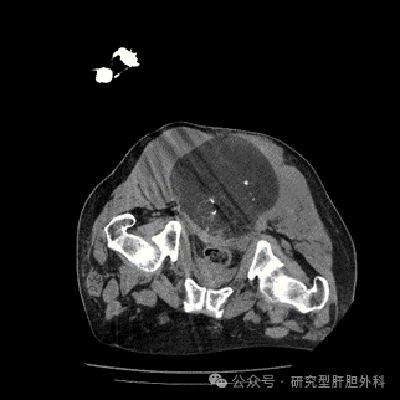

通常情况下,脊索瘤的治疗以手术治疗为主。由于该患者无法完整手术切除肿瘤,科室讨论最终决定采用冷冻消融来实施治疗,对于此巨大肿瘤,拟采用多点布针,先大后小,多次消融的方式,逐步减少肿瘤负荷,为靶向、放疗等提供良好的手术机会。

治疗过程CT图像